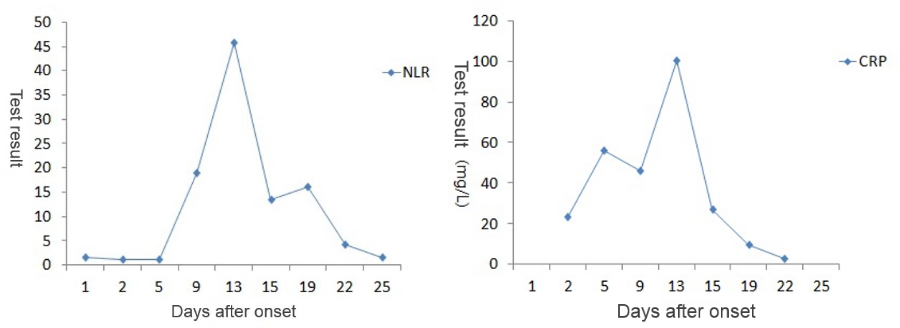

During the whole process of diagnosis and treatment, the patientŌĆÖs clinical manifestations and chest CT scan results have been recorded (see Table 1), and so are CBC and CRP results (see Figure 1).

As the patientŌĆÖs health deteriorated, the white blood cell count (WBC#) and neutrophil count (Neu#) increased sharply after a slight decline, while the lymphocyte count (Lym#) continued to decline. The Neutrophil-to-Lymphocyte Ratio (NLR) rose rapidly while the CRP value goes up. At the most critical moment (the 13th day after the onset of symptoms), WBC#, Neu#, NLR and CRP reached their peaks respectively, with Lym# at the lowest point.

After proper medical treatment and caring, the patient gradually recovered, with rapid decline of WBC#, Neu#, NLR and CRP. In contrast, Lym# gradually increased. On the 25th day, WBC#, Neu#, NLR, Lym# and CRP all returned to normal range. Although CT scan showed that the lesions in lungs hadnŌĆÖt completely disappeared yet, the patient was already able to move without oxygen therapy. Most importantly, the nucleic acid test result turned negative.

An NLR greater than 3.13 can be used as an independent predictor for the exacerbation of patients with COVID-19. The finding of this case is consistent with that in the study published by Ditan Hospital. The patientŌĆÖs NLR was higher than 3.13 from the 9th day to the 22nd day, and the NLR drops below 3.13 on the 25th day. In this case, PCT was monitored on Day 5, 13, and 22, all of which were lower than 0.5 ng/mL, indicating that no serious bacterial infection occurred.

The CBC and CRP change exactly in line with the law of disease development during the diagnosis and treatment of COVID-19 patients. Monitoring these routine laboratory test results, including WBC, Lym#, NLR and CRP, during the hospitalization period is helpful for managing patientŌĆÖs medical treatment and prognosis.